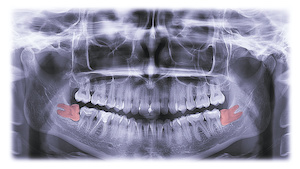

Each patient’s situation is unique. Your oral surgeon will usually take a panoramic X-ray to determine whether your wisdom teeth will need to be removed. If he or she recommends the removal of your wisdom teeth, it is best to have them removed sooner rather than later.

When your child sees your dentist for regular checkups, they will monitor wisdom tooth growth through X-rays or other diagnostic scans. Once your dentist feels the time is right for wisdom teeth removal, they will refer you to a surgeon for treatment.